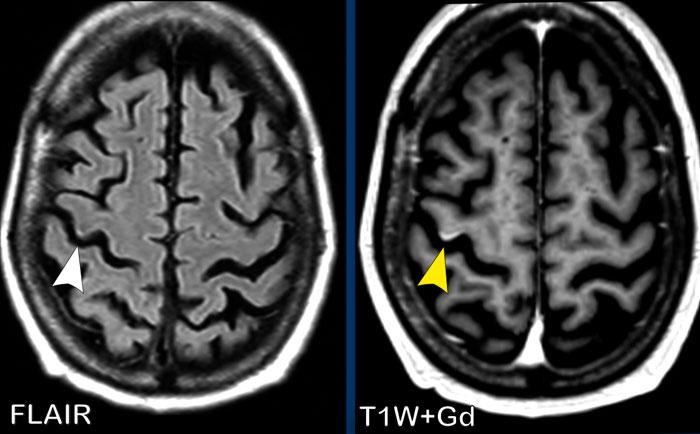

Đây là một ví dụ khác về ngấm thuốc dạng vòng hở tại cầu não ở bệnh nhân mất myelin.

Các hình ảnh này của một phụ nữ 52 tuổi đang được điều trị bệnh bạch cầu cấp dòng tủy (AML), nay nhập viện với triệu chứng liệt tay phải và khó tìm từ ngữ.

Hình ảnh

Trên chuỗi xung T1W có tiêm thuốc tương phản từ, có một tổn thương giảm tín hiệu không có hiệu ứng khối, với ngấm thuốc không hoàn toàn của thành tổn thương. Chỉ phần ngấm thuốc của tổn thương mới có hạn chế khuếch tán (đầu mũi tên).

Kết luận

Chúng tôi đánh giá đây là tổn thương mất myelin với ngấm thuốc dạng vòng hở.

Kết quả cho thấy đây là bệnh lý não chất trắng đa ổ tiến triển (PML – Progressive Multifocal Leukoencephalopathy), một rối loạn mất myelin do nhiễm virus JC cơ hội ở bệnh nhân suy giảm miễn dịch nặng.